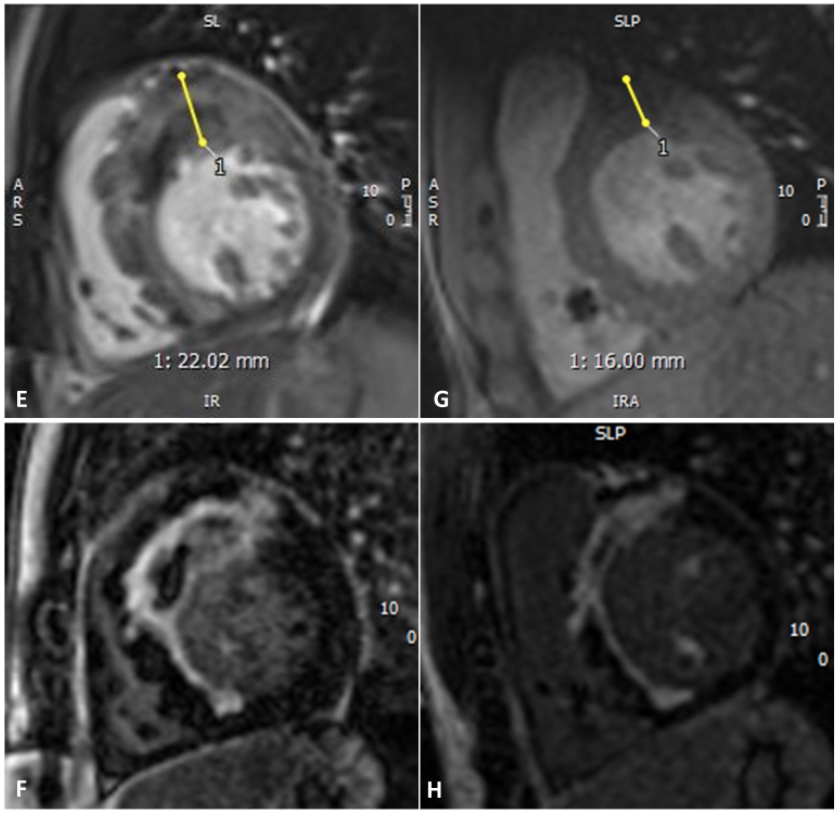

Figure 3. (E), (F) CMR performed eight weeks after the acute event. (E) Cine short-axis basal slice showing maximum wall thickness of 22 mm; (F) Late gadolinium enhancement (PSIR), short-axis basal slice. (G), (H) One-year follow-up CMR. (G) Cine short-axis basal slice showing maximum wall thickness of 16 mm; (H) Late gadolinium enhancement (PSIR), short-axis basal slice..jpg)